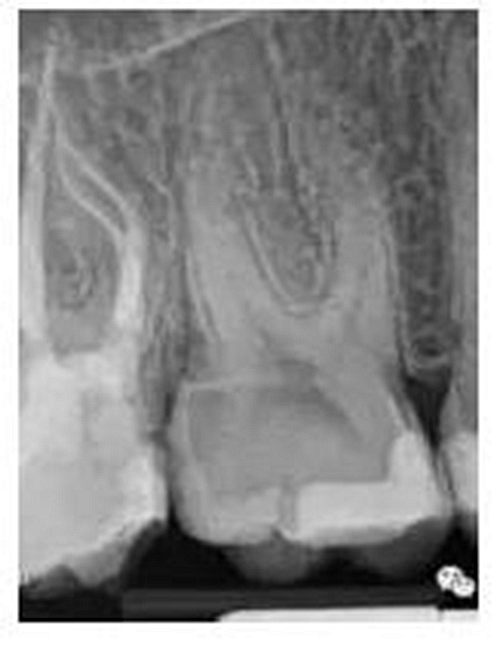

最后來玩一個根管治療質(zhì)量的評估——下圖是武大彭彬教授的一個病例,仔細(xì)觀察可以挑出一點問題,但問題事出有因!看看你的“眼力”如何——問題在那里?教授的專業(yè)水平是不用懷疑的,那么事出的原因可能是什么?

問題答案:這個病例的問題主要反應(yīng)在開髓的洞形修整,注意觀察該牙X-RAY的左側(cè)洞壁,如果常規(guī)情況制備成這樣是由于裂鉆破壞了洞壁和洞底所形成的臺階。如果評估根管治療的質(zhì)量那是要扣分的!但這個病例仔細(xì)觀察洞壁形態(tài)就可以看出:該病例屬于再治療的病例,因此還是屬于一個理想的病例。